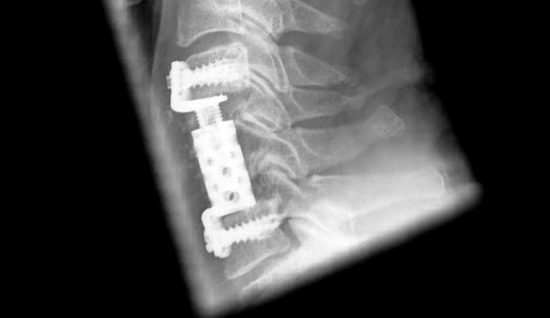

Corpectomía C5 + C6, descompresión y reeemplazo de cuerpo vertebral. Buena valorabilidad del canal vertebral y la médula espinal pese al implante de titanio

Dada la mielopatía clínica y de imagen, se indicó la descompresión extensa del canal vertebral cervical. Esto debería lograrse mediante una corpectomía de C5 y C6 y un implante de reemplazo de cuerpo vertebral con tornillos con espiga expandible desde anterior.